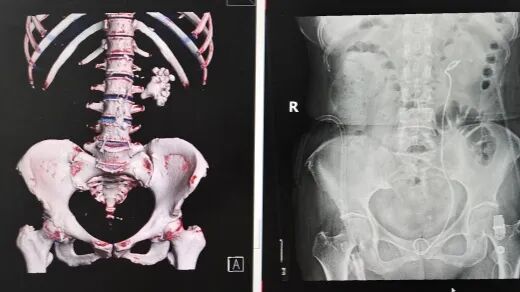

患者鄭奶奶因突發(fā)腰痛前往醫(yī)院就診,經(jīng)CT檢查結果顯示,其左腎已被結石完全填充,確診為典型的腎鑄型結石。腎鑄型結石因形態(tài)酷似鹿角,又被稱為鹿角形結石,這類結石會在腎臟內長期生長,逐漸填滿腎臟內部空間形成整體形態(tài)結石,不僅治療處理難度極大,還伴隨極高的感染風險。

針對鄭奶奶這一復雜病例,常規(guī)手術方式通常需分次操作,且要在腎臟上人為開鑿多個孔洞,將結石分塊擊碎后再逐一取出。這種傳統(tǒng)手術方式不僅會對患者身體造成較大創(chuàng)傷,還會延長術后恢復時間。為最大程度減輕患者痛苦,保障手術安全與效果,泌尿外科博士團隊在術前展開周密準備工作:通過詳細檢查充分評估結石分布范圍、大小形態(tài)及腎內結構情況,反復研討制定出科學周密的個性化手術方案。

手術當天,科室副主任喻衛(wèi)東及手術團隊在超聲精準引導下,為患者建立起一個僅筷子粗細的微創(chuàng)小隧道,直達腎臟內結石位置。隨后,利用醫(yī)院最新引進的高效率碎石設備——氣壓彈道碎石機,將腎盂內的結石逐一擊碎并吸出。在手術過程中,面對部分藏于腎臟角落的細小結石,喻衛(wèi)東創(chuàng)新性地采用可彎曲軟鏡,靈活調整軟鏡角度,巧妙 “拐進” 腎臟角落,耐心將隱藏結石勾出至視野清晰區(qū)域后,再進行精準擊碎處理。經(jīng)過團隊的不懈努力,最終在僅保留單一微創(chuàng)通道的前提下,實現(xiàn)了腎臟內結石的 “無死角” 清理。術后,鄭奶奶生命體征平穩(wěn),恢復狀況良好。